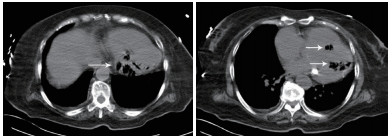

患者女性,75岁。因“被发现晕倒在地伴大小便失禁6 h余”于2018年10月25日12:10入院。患者为独居老人,当晚失联,入院6 h前,家人在家中发现其神志不清,大小便失禁,卧于床边,后患者家属呼120送至本院急诊科。入院后详细追问病史,患者身边无药瓶,家中亦无煤烟味。既往有“冠心病陈旧性心肌梗死、高血压病、2型糖尿病”病史11年余,“卵巢癌术后放化疗”病史2年余,“直肠占位”病史半年余。入院急诊体格检查:体温36.0℃,脉搏80次/min,呼吸17次/min,血压108/52 mmHg(1 mmHg=0.133 kPa),老年女性,神志不清,烦躁,面色苍白,皮肤湿冷、散在花斑,皮肤黏膜无破损。双侧瞳孔等大等圆,对光反射存在,言语、伸舌及肌力检查不合作,双肺呼吸音清,未闻及干湿性啰音,心率80次/min,律齐,心脏各瓣膜听诊区未闻及杂音,肝脾肋下未及,双下肢无水肿,四肢可见不自主活动,双侧病理征未引出。入院后心电图提示肢体导联及胸导联均有T波低平或倒置,V4-V6导联ST段压低(图 1)。血常规:白细胞计数32.35×109/L,中性粒细胞比率84.7%,中性粒细胞计数27.4×109/L,血红蛋白64 g/L,血小板计数221×109/L;CRP 111.9 mg/L,PCT > 100 ng/mL;肌酸激酶1 847 U/L,肌酸激酶同工酶356 U/L,肌酐219 μmol/L,肌钙蛋白T 6 257 pg/mL,NT-proBNP > 35 000 pg/mL。入院后急查颅脑、胸部及全腹CT,胸部CT提示左心室、室间隔及肺动脉根部区域见不规则条状、条片状低密度影,参考CT值约-200~-900 HU(气体密度影),外周伴伪影,左心室为著,外周分布为主,似累及心肌区域,部分心肌变薄,心包区域尚连续,主动脉系统未见气体影(图 2~3)。12:45患者病情急剧进展,呼吸心搏骤停,予气管插管、心肺复苏及药物抢救治疗,13:25抢救无效临床死亡,患者家属拒绝尸检。

| 示左心室、室间隔见不规则条状、条片状低密度影,参考CT值约-200~-900 HU,提示为气体影,左心室为著,外周分布为主,似累及心肌区域,部分心肌变薄,心包区域尚连续(白色箭头所示) 图 2 患者胸部CT结果 |

| 示气体影以左心室为著,外周分布为主,似累及心肌区域,部分心肌变薄(黑色箭头所示) 图 3 患者胸部CT冠状位影像 |

本例患者恶性肿瘤、糖尿病病史等使患者免疫功能低下,易合并重症急性感染。胸部CT显示左心室、室间隔及肺动脉根部区域见不规则条状、条片状低密度影,测量CT值提示为气体密度影。2016年Laiq等[1]曾报道因感染性心内膜炎致患者左心室内气体形成一例,患者血培养提示柠檬酸杆菌生长,最终患者发生急性心力衰竭,紧急二尖瓣置换术,术后乳头组织同样培养出柠檬酸杆菌,经抗感染治疗预后良好。2014年Alladina等[2]也曾报道一例因播散性肺克雷伯杆菌感染、产气,气体进入血液系统引起的脑空气栓塞。另外,临床工作中某些有创诊疗中,如深静脉置管、肺穿刺活检等也可能引起心脏空气栓塞[3-4]。但本例报道患者脑动脉、主动脉等大动脉系统未见明显气体影,说明患者左心室内气体不具有流动性。仔细观察胸部CT影像学表现,气体在左心室内主要沿室壁分布,部分心肌壁变薄,综合考虑为左室心内膜炎可能。左室内气体位于心内膜下,不在心腔内,故不具备游走性,这也就能解释为何患者其他动脉系统血管内不存在气体的原因。

本例患者存在重症急性感染,烦躁、皮肤湿冷、皮肤散在花斑,提示患者可能存在感染性休克,急性感染累及心内膜、心肌导致心内膜炎、心肌炎,细菌产气引起心内膜下气体形成。但遗憾的是,患者病情进展迅速,患者家属拒绝尸验,无法获得进一步临床资料。死亡原因推测可能为感染性休克,加之感染侵蚀患者心内膜,心肌使心肌变薄,最终引起心脏破裂或心内膜下气体破入心腔内引起空气栓塞而死亡。